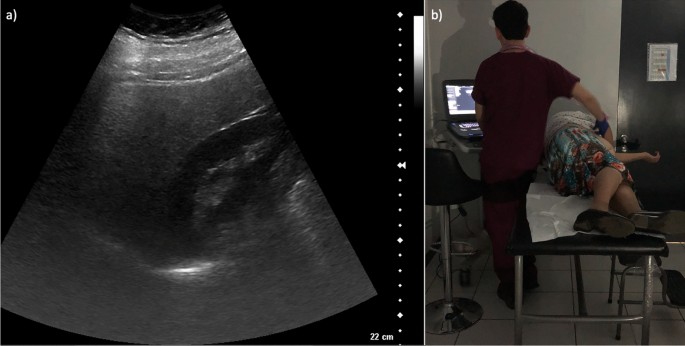

(a) Still ultrasound image (static photograph) of the liver demonstraing that the liver and the kidney were captured on the same plane. (b) A Chile BiLS technician performing an ultrasound on a participant.

Using computer-generated randomization, we selected a random subset of 425 (~ 10%) participants from the 4032 participants with baseline images available in 2019 (Fig. 1) to assess agreement in identifying liver steatosis. The evaluation involved comparing the findings for hepatic steatosis from the original ultrasound examinations done by eight Chile BiLS radiology technicians (original readings) with the interpretation of a radiologist from Baylor College of Medicine (observer 1), who reviewed still digital ultrasound images taken during the examination. Blinded duplicate images from 34 randomly selected participants (10% of the original subset, which was slightly lower than the 425 finally included) were included to assess reliability. This duplicated set of images was re-evaluated by observer 1 and by two Chile BiLS radiology technicians (observers 2 and 3). Observers 2 and 3 were part of the eight radiology technicians who generated the original readings and contributed four of the readings (three from observer 2 and one from observer 3) to the random set of 425. However, they did not conduct any of the examinations for the participants included in the set of 34 with blinded duplicate images. Finally, observer 2 re-evaluated the duplicated set of 34 images to assess intraobserver agreement (Fig. 2).